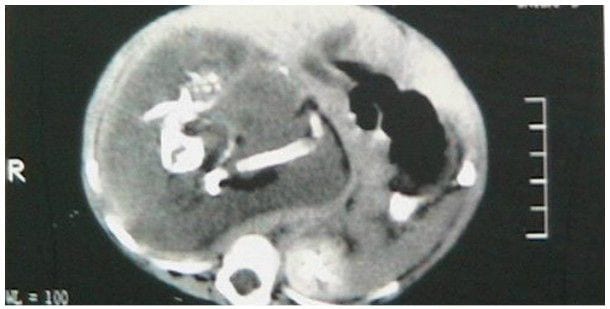

Początkowo zmiany, jakie zaobserwowano u nowo narodzonej Chinki, lekarze uznali za guz. Jakież było ich zdziwienie, gdy okazało się, że to nie guz, a podwójna ciąża. Wykryte płody miały osiem i dziewięć tygodni. Było to jednocześnie fascynujące, jak i przerażające odkrycie. Lekarze stwierdzili, że najprawdopodobniej „dzieci” noworodka to tak naprawdę wchłonięte przez płód rodzeństwo. Takie przypadki zdarzają się w czasie ciąż bliźniaczych – raz na 500 tysięcy ciąż.